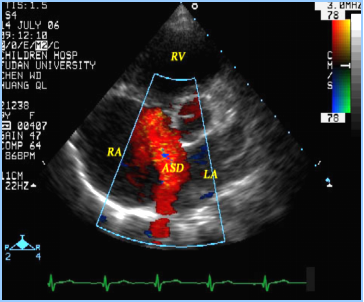

房间隔缺损:超声心动图表现

房间隔缺损(继发孔型)